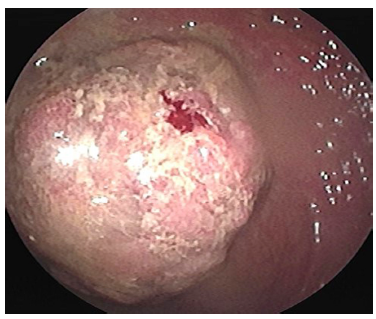

Un mes después, por el pólipo descrito en el ángulo hepático sin posibilidad de resección endoscópica, se realizó una hemicolectomía derecha e ileotransversostomía, con un reporte histopatológico de 2 adenomas tubulares con displasia de alto grado focal sin compromiso pedicular, bordes de resección libres de lesión y sin compromiso ganglionar. 2 meses después, en la colonoscopia total de seguimiento se encontró, además de los cambios posquirúrgicos, un pólipo sésil de 40 x 20 mm en el colon transverso inmediatamente distal a la anastomosis (biopsia: adenoma velloso con displasia de bajo grado) (Figura 4); debido a este hallazgo, se llevó a una nueva cirugía con ampliación de la colectomía, omentectomía y nueva anastomosis ileocolónica con un reporte histopatológico de adenoma tubulovelloso con displasia de alto grado y adenocarcinoma in situ inmediatamente distal a la anastomosis previa, sin signos de infiltración, bordes de resección libres, sin compromiso ganglionar ni del omento mayor. 6 meses después se realizó una nueva ileocolonoscopia con un único hallazgo de pólipo de 4 mm en el recto superior resecado con asa fría (patología: adenoma tubulovelloso con displasia de bajo grado) (Figura 5).